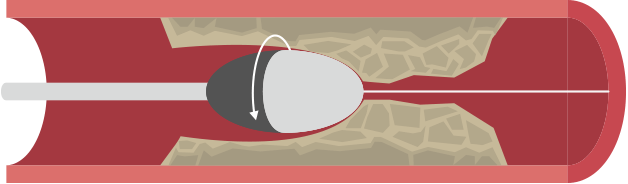

ガイドワイヤーをカテーテルに通して冠動脈内に挿入し、狭窄部や閉塞部を通過させます(図a,b)。ガイドワイヤーは、バルーンカテーテルなどの機器が冠動脈内を走行するためのレールの役割をします(図c)。

ガイドワイヤーの挿入 図a 図a

ガイドワイヤーの挿入 図b 図b

ガイドワイヤーの挿入 図c 図c